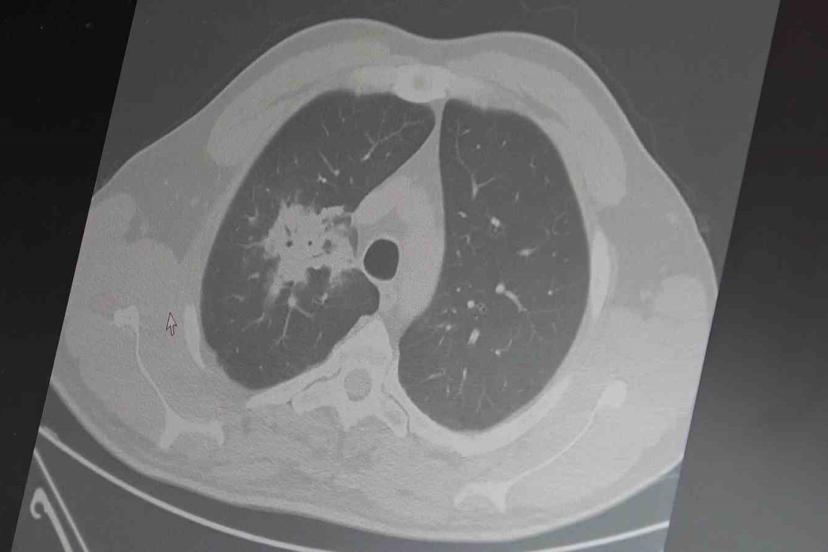

100’den fazla bilimsel çalışmanın incelendiği kapsamlı analizlere dikkat çeken Özkaya, elektronik sigaraların özellikle temas ettiği akciğer ve ağız bölgelerinde kanser riskini artırabileceğine dair güçlü bulgular bulunduğunu belirtti. Uzun vadeli sonuçların henüz tam olarak ortaya çıkmadığını ancak erken uyarı işaretlerinin ciddi olduğunu vurguladı. Araştırmalarda insan, hayvan ve laboratuvar verilerinin birlikte değerlendirildiğini aktaran Özkaya, elektronik sigaraların içerdiği kimyasalların hücre düzeyinde zarara yol açtığının ortaya konulduğunu ifade etti.

2024 yılında yayımlanan bir çalışmaya da değinen Özkaya, hem geleneksel sigara hem de elektronik sigara kullanan bireylerde akciğer kanseri riskinin, sadece sigara içenlere göre dört kat daha fazla olduğunun bildirildiğini kaydetti.